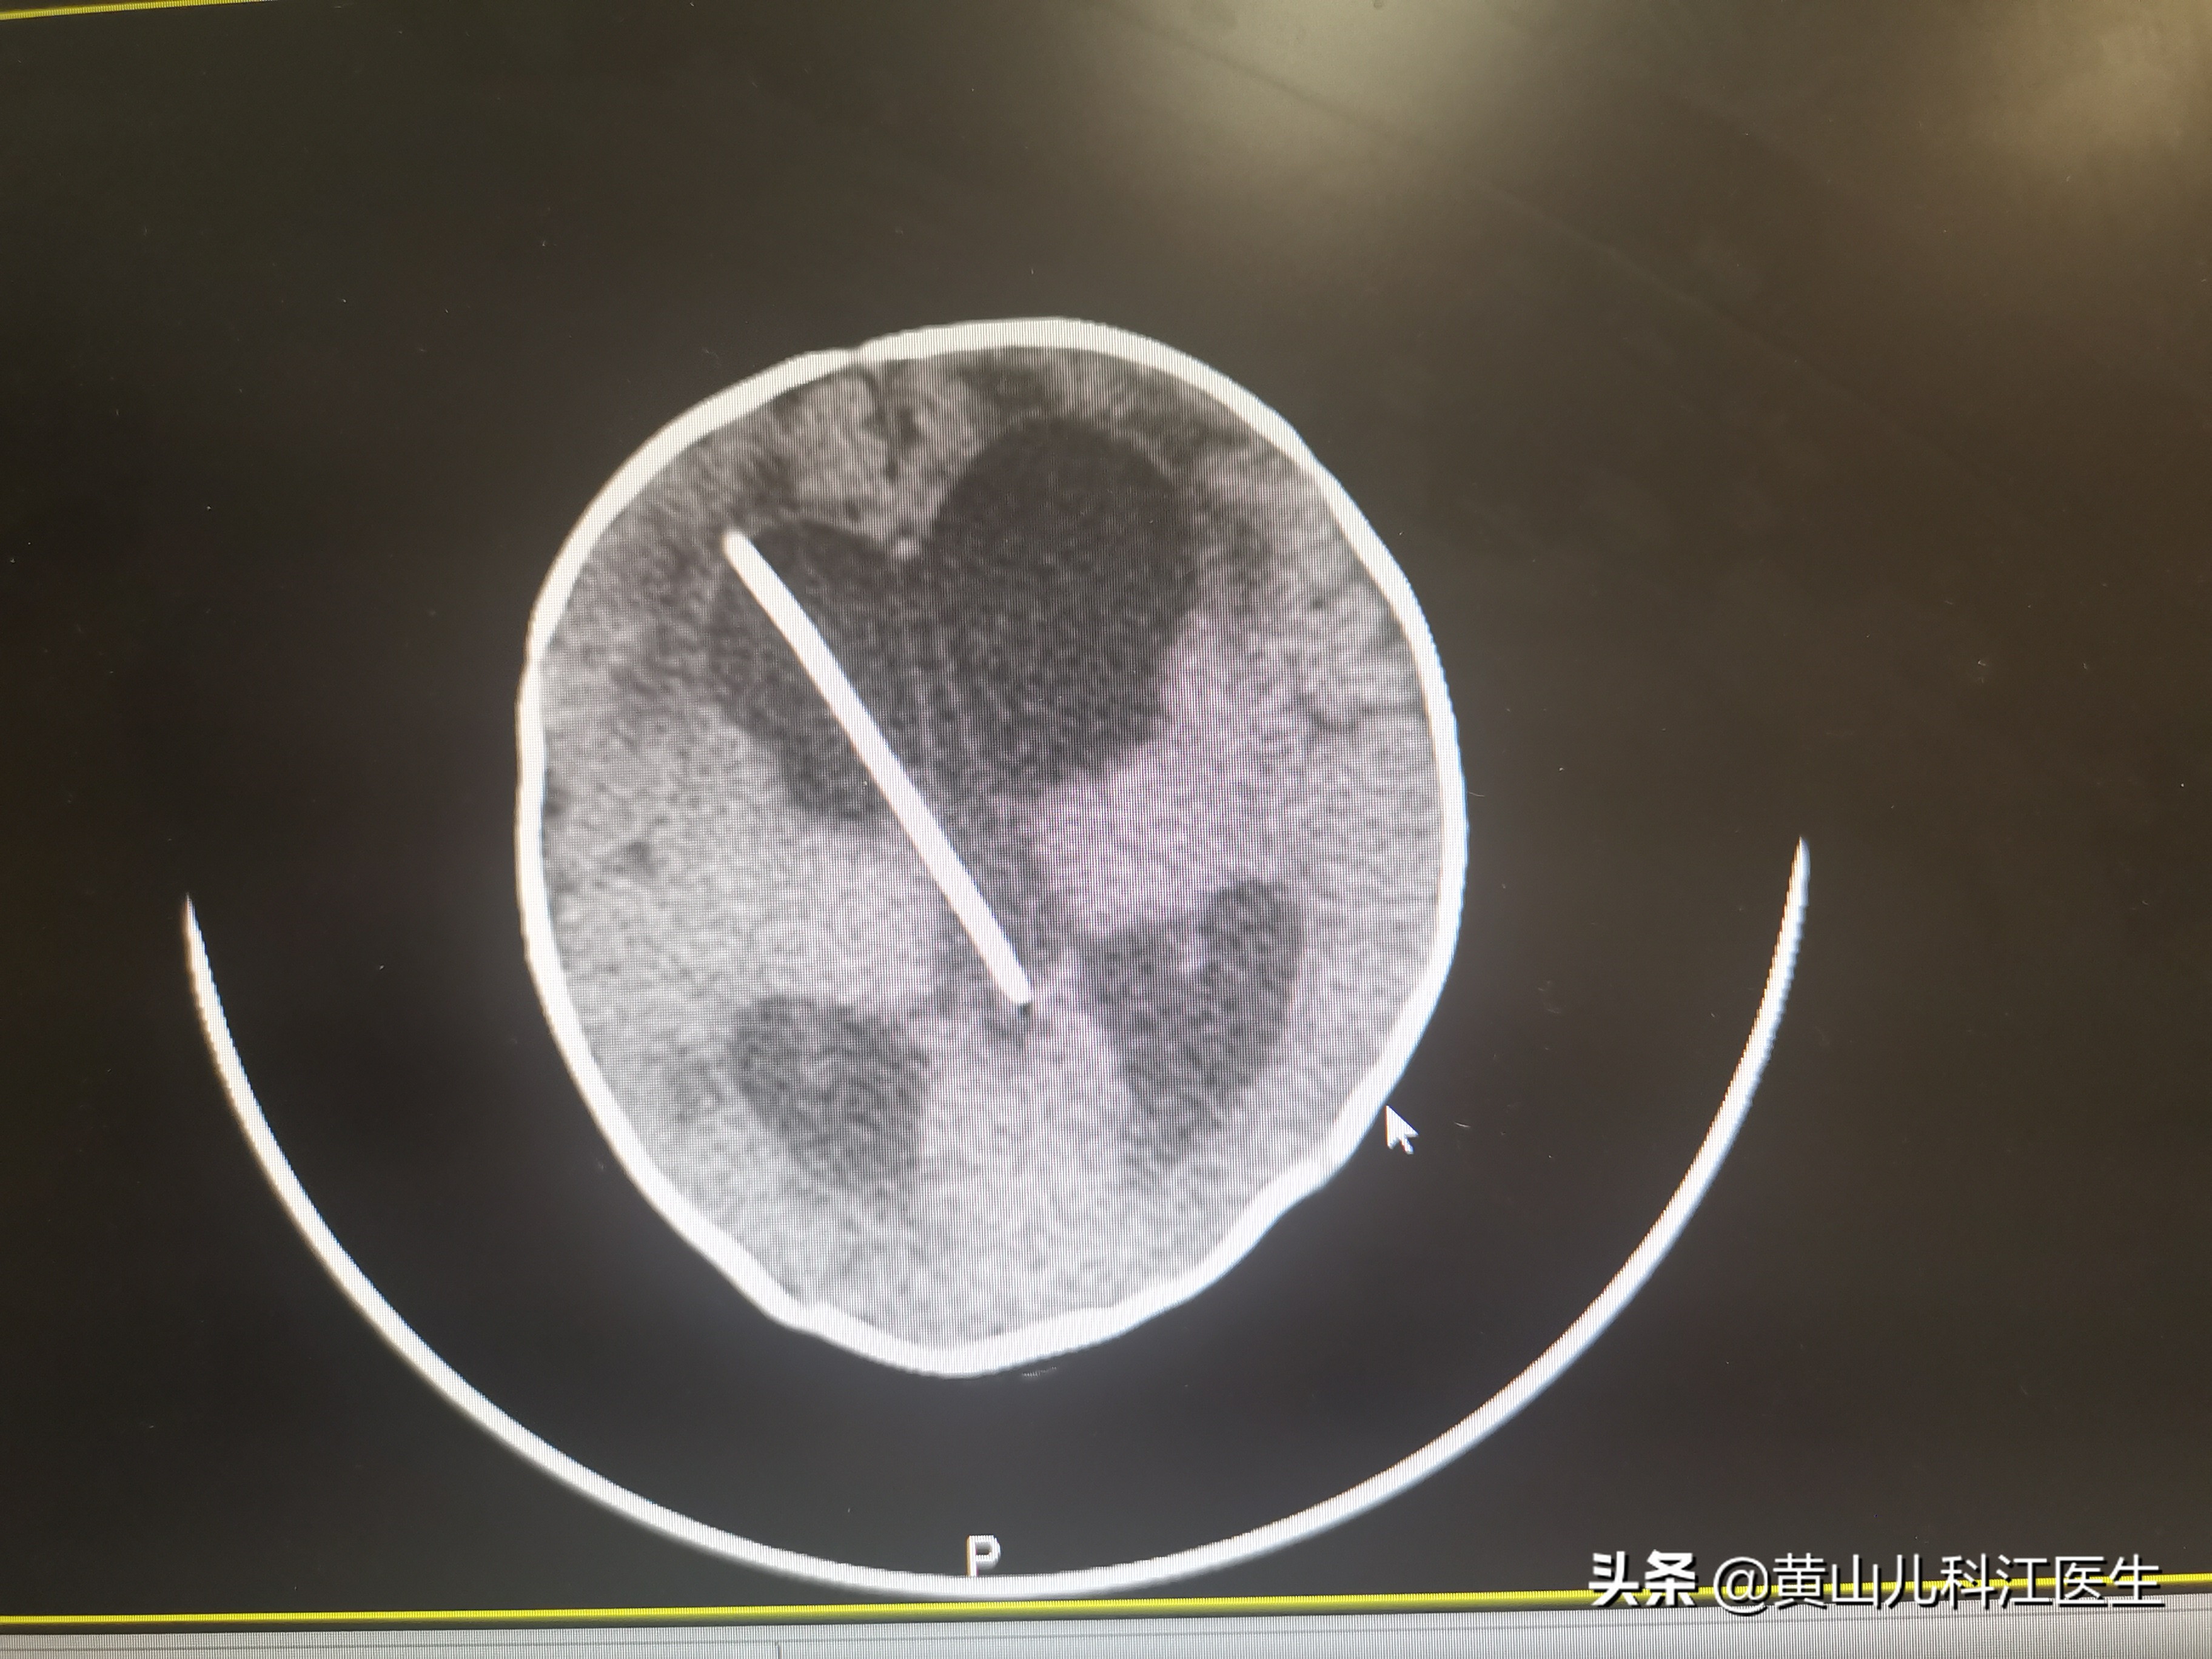

- 并发梗阻性脑积水如果不加干预,脑脊液增多,颅内压增高可引起脑疝,压迫脑干将导致呼吸、心跳停止。所以细菌性脑膜炎后脑积水的干预主要采用外科手段,外科治疗有三种方式,即脑室外引流、脑室-腹腔分流术、第三脑室造瘘术(EVT)。

- 脑室外引流:细菌性脑膜炎并发脑积水且脑积液生化异常不适合立即行分流术,因此一般先在颅内植入Ommaya囊,外引*脑流**脊液,在脑脊液恢复正常后再进行脑室-腹腔分流或第三脑室造瘘术。

- 脑室-腹腔分流术:是目前应用范围最广的外科治疗术式。分流管起点在侧脑室,经头、颈、胸、上腹部的皮下隧道,分流管末端放置在下腹游离腹腔内。需要注意该术常见并发症有腹腔内感染、颅内感染、分流管堵塞及位置异常。而且随着生长发育的进行,需要多次换管,给孩子身心健康带来压力。

脑室-腹腔分流术 分流管上端置于侧脑室